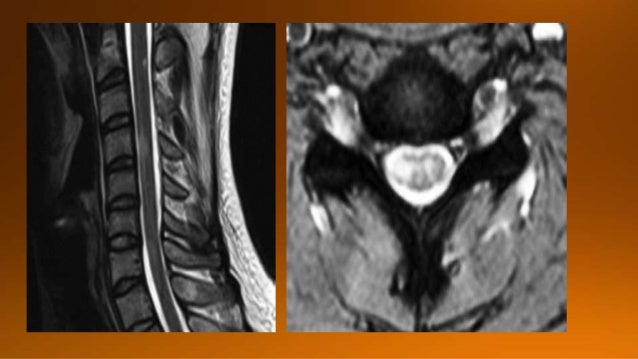

2. 2. In this presentation we will focus on spinal cord diseases that are characterized by high signal within the cord onT2WI. The most common causes are degenerative compressive myelopathy, inflammatory and demyelinating disorders.

9. 9. MS: short segment focal wedge-shaped involvement of the posterior column of the spinal cord with typical periventricularWM-lesions.

10. 10. Usually in cervical spine

11. 11. On transverse images MS lesions typically have a round or triangular shape and are located posteriorly or laterally